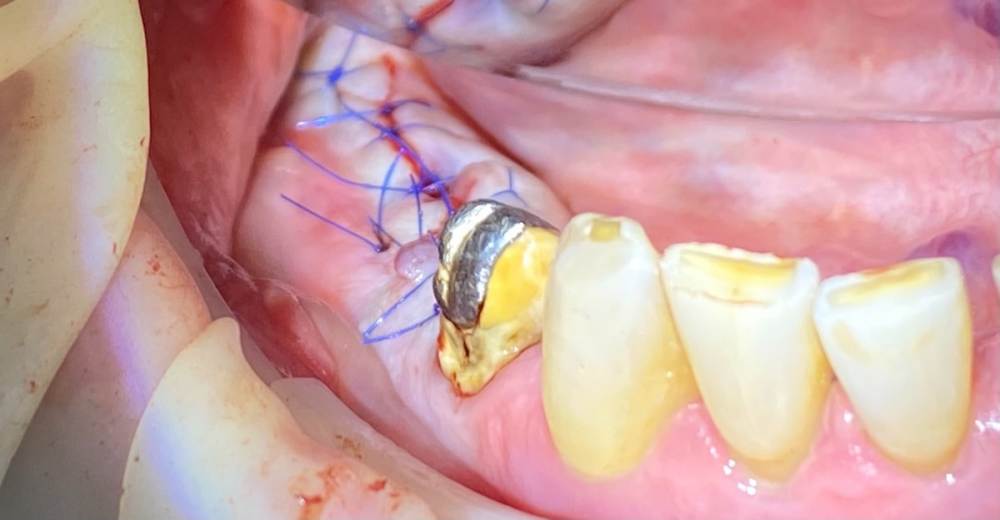

А вот снизу вариантов кроме одностороннего съёмника или имплантации не было. Поэтому план: удалить 4.6, выскрести всю гадость, имплантация 4.5-4.7 и мостовидная конструкция в будущем, также планировал работу с десной, но скелетировав кость понял, что биотип толстенный и нет в этом смысла.

Кость D1. Очень старался не перегреть.

Пациент бросающий курильщик (хорошо хоть не барабанщик), поэтому заглушка, швы. Хотя торк около 50, имплантиумы, 4.5 на 10 и 8 соответственно.

Немного аутокости со сверла уложил в области 4.7.